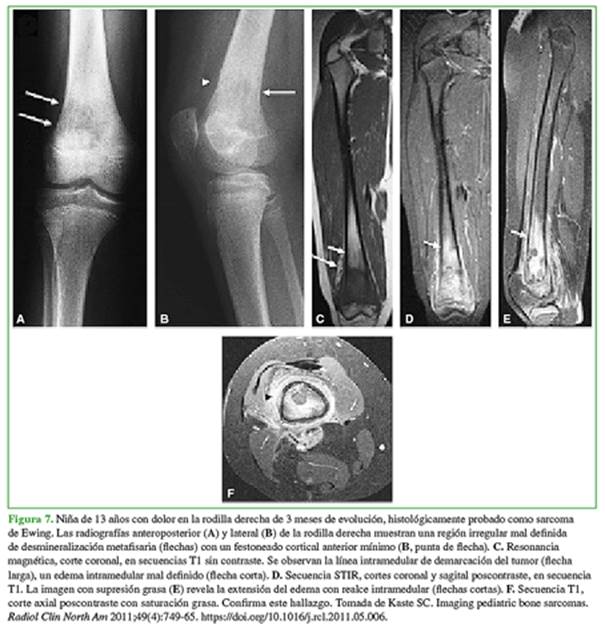

Los diagnósticos diferenciales más frecuentes son: sarcoma de Ewing y osteomielitis (Figuras 7 y 8).